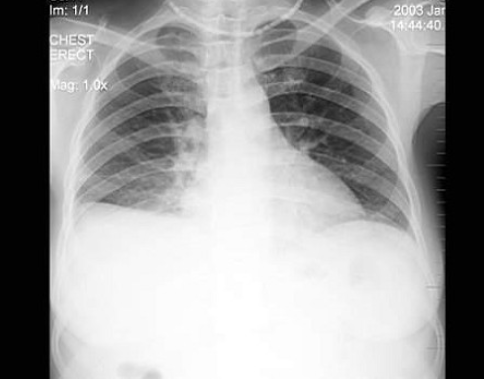

75、单项选择题

男,45岁,发热、咳痰1月余,结合图像,最可能的诊断是()

A.肺脓肿

B.肺结核

C.吸入性肺炎

D.肺囊虫病

E.肺癌